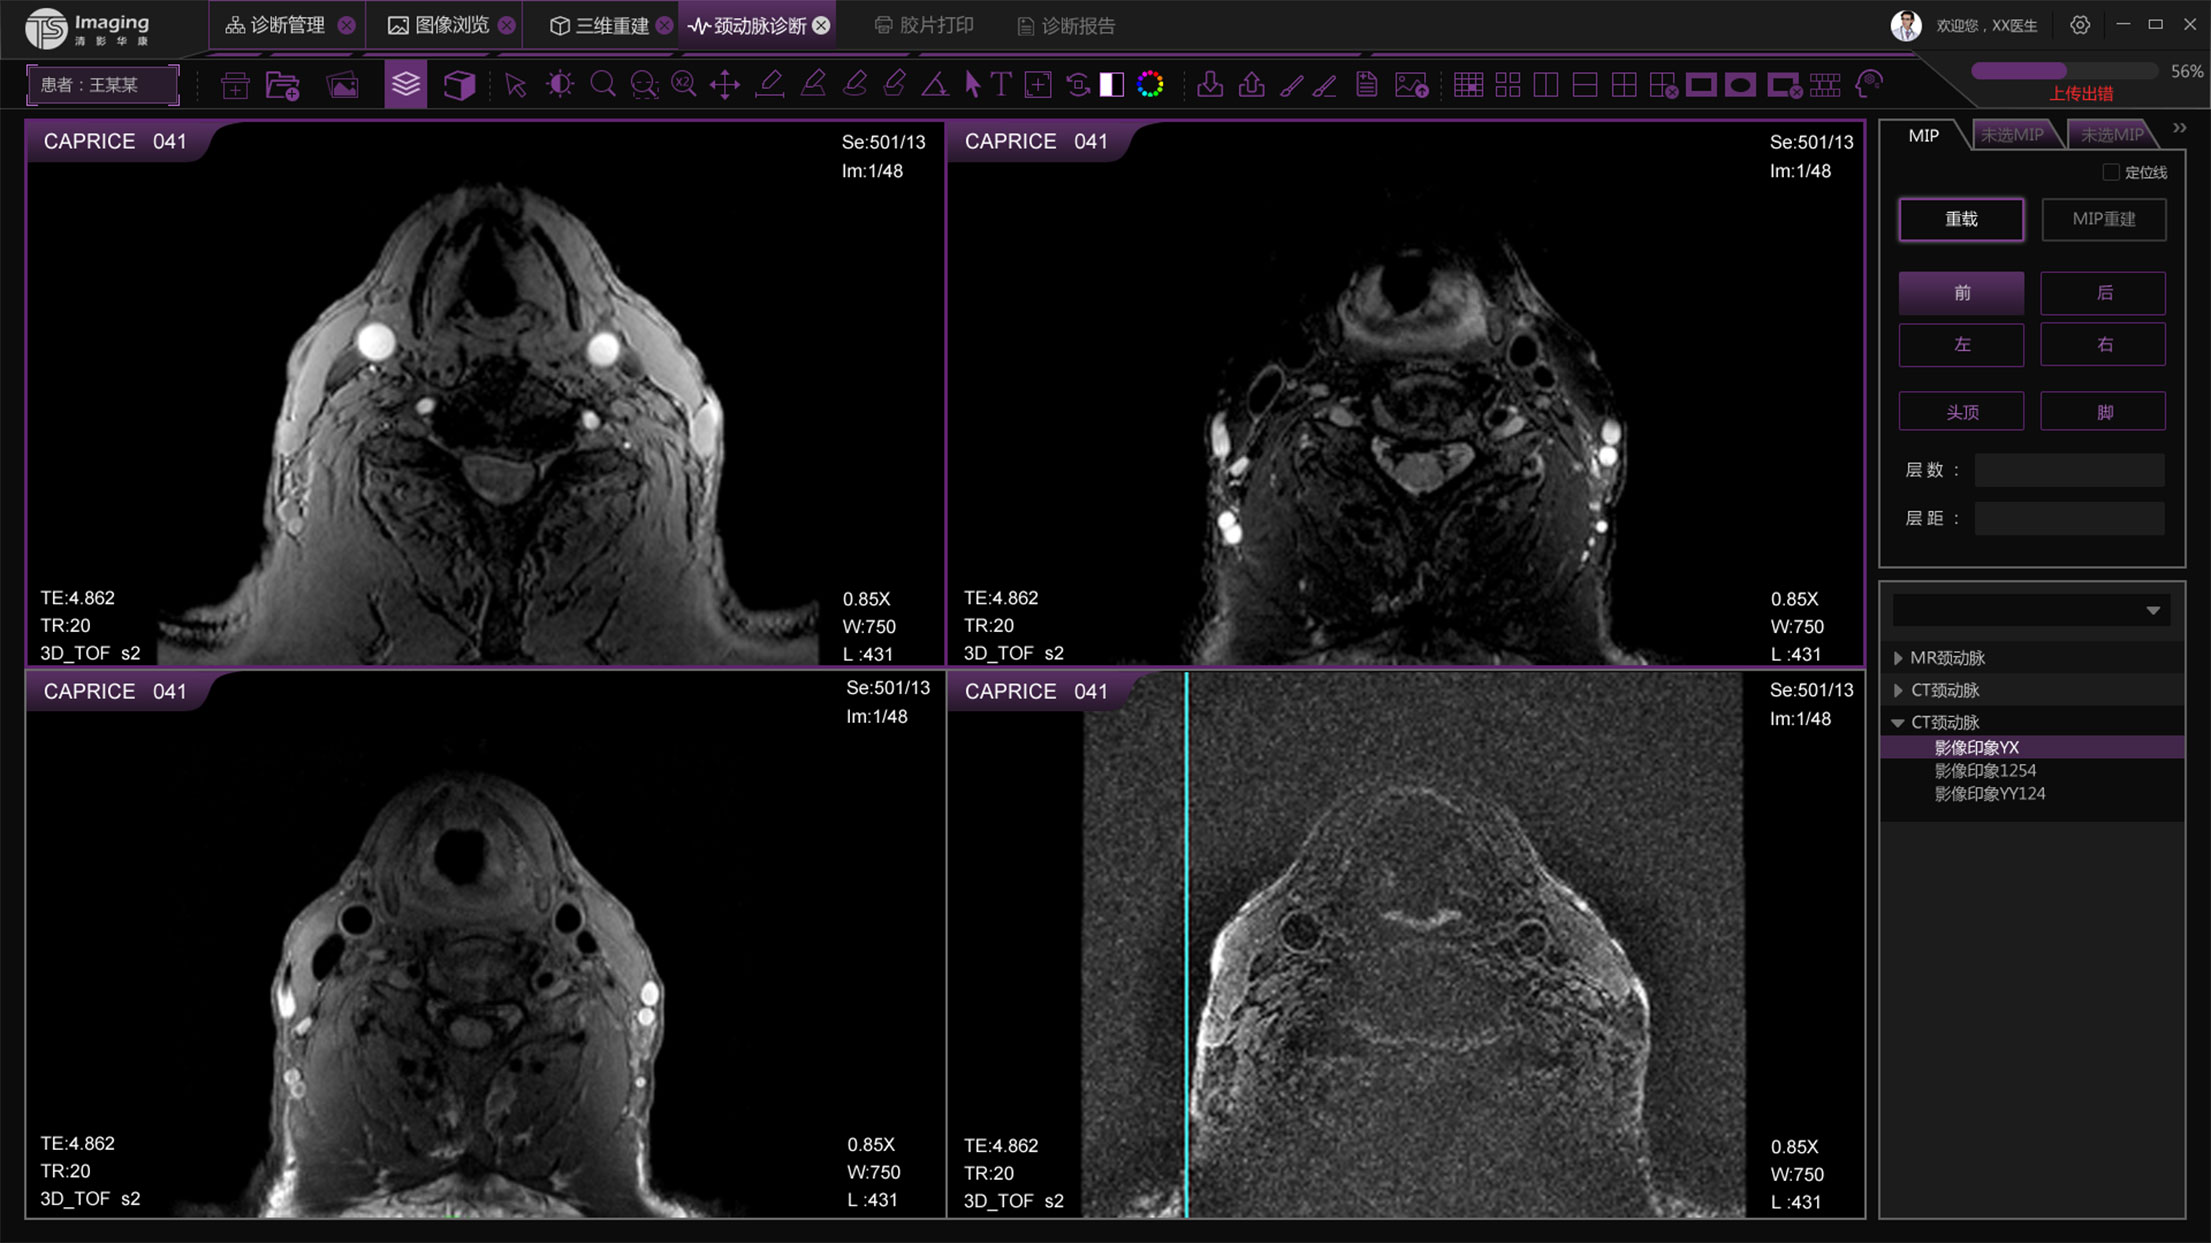

頸動脈診斷頁面

頸動脈診斷頁面整體布局和三維重建比較相似,最大的區(qū)別是右側(cè)的操作區(qū)域,血管分析都為按鍵操作,通過間隔的大小分成三部分。單層切片除了按鍵還有下拉菜單的操作。